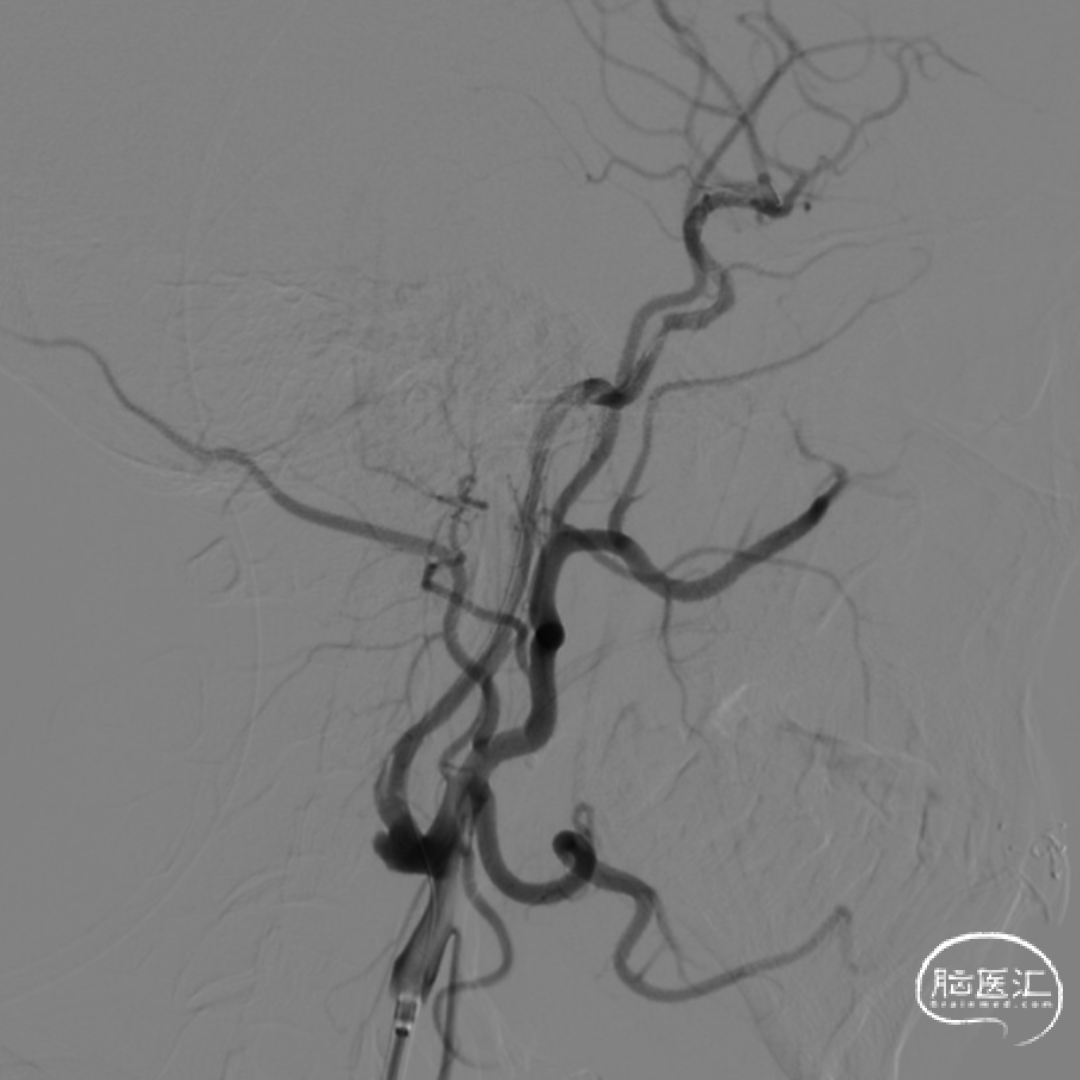

· 沿5F Tethys®中间导引导管送入3.5-5.5mm×300cm 保护伞于C5段释放,同轴送入Sterling 4.0mm×30mm 球囊扩张导管并覆盖C1段最狭窄处理,以14atm扩张维持约5秒并迅速释压,观察约1分钟患者心率及血压无明显变化,且意识及肢体功能无明显改变,复查造影示C1段狭窄较前明显改善。

· 撤出球囊导管送入7.0×40mm 自膨式支架,在路图及造影下定位,于狭窄处释放,再次造影提示C1段残余狭窄<10%,保护伞处近端造影剂充盈欠佳。

· 遂再次送入 3.0×12mm SacSpeed®球囊扩张导管于C1段远端以8atm扩张,并逐渐释放,同时跟进中间导管至C5段,继续前送中间导管在负压抽吸下将保护伞回收至中间导管内,并持续负压下将保护伞撤出,保护伞及抽吸注射器内无明显血栓碎片,撤出中间导管、8F Guiding。